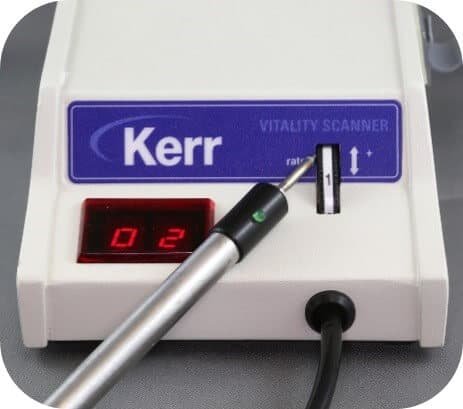

Electric pulp testing (EPT)

The electric pulp test uses electrical current to assess pulp vitality. It is especially useful for teeth with no visible response to thermal tests.

Procedure

- A small electrical current is passed through the tooth using a probe/sensor.

- The current is adjusted and the patient reports whether they feel a sensation.